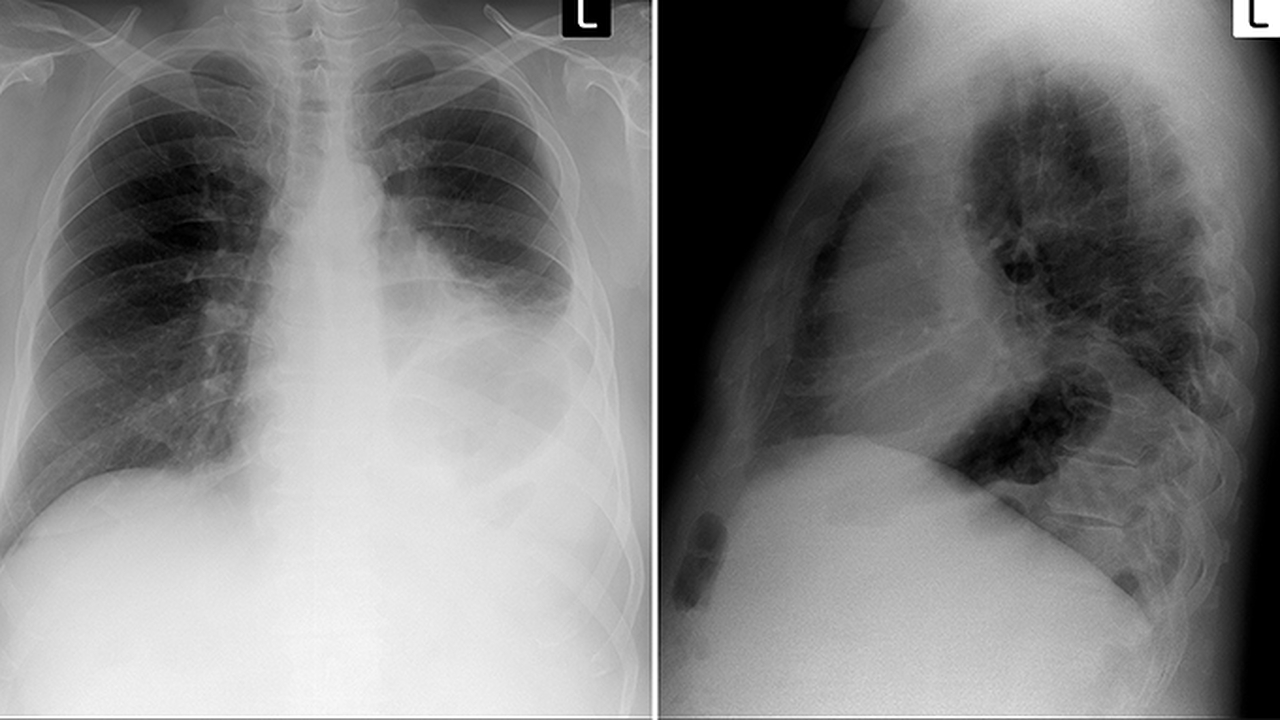

肺癌是一種常見(jiàn)的惡性腫瘤,其發(fā)病原因復雜,包括吸煙、環(huán)境污染、職業(yè)暴露等多種因素。早期診斷和規范治療對提高患者生存率至關(guān)重要。